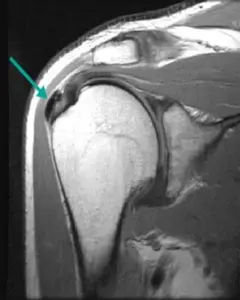

3. MR (Manyetik Rezonans)

Bazı durumlarda, MR taramaları da kullanılabilir. MR, dokuların ayrıntılı görüntülerini sağlar ve kalsifik tendinitin derecesini belirlemeye yardımcı olabilir.